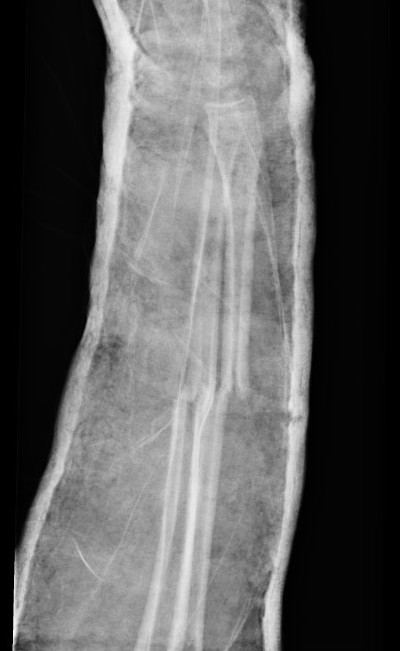

3. Intramedullary elastic nail

TENS technique

Technique

Radius (typically first as more difficult to reduce)

Entry point with awl 2 cm proximal to distal physis

1. Radial styloid / distal lateral entry

- ensure radial nerve / cephalic vein, 1st extensor compartment protected

2. Listers tubercle / dorsal entry

Elastic Nail size

60 - 70% of the intramedullary canal

Typically 1.5 - 2.5 mm

Fracture reduction

Avoid passing nails incorrectly multiple times as may cause compartment syndrome

Bend tip of elastic nail

May need small open reduction

Cut nail

Withdraw 1 cm, cut with endcutter, then advance

Ulna (usually reduced after radius fixation)

Entry point 2 cm distal to apophyseal plate

1. Proximal lateral

- avoids ulna nerve

3. Distal medial

Postoperative

Cast in supination to tighten interosseous membrane

Cast 6 weeks

Removal of TENS at 4 - 6 months once osseous union established